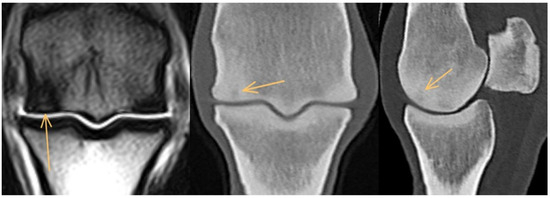

3.3. Proximal Sesamoid Bones